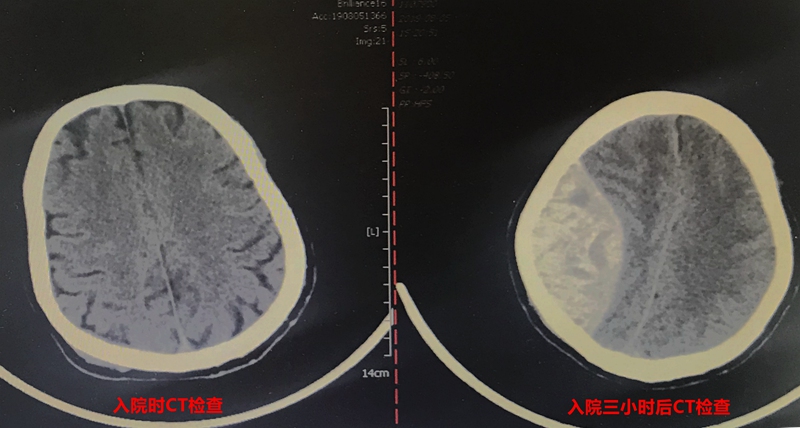

刘先生今年49岁,家住玉环,日前,他在骑电动车上班时被货车撞倒。当下刘先生有些神志不清、恶心呕吐,但送来医院时,意识已经恢复。头部看着没什么出血,接受止血补液等对症治疗后,他和家人刚安心。头颅CT检查却显示右侧顶部颅板下小出血灶,伴局部颅骨骨折。

中午12时许,刘先生被收住入院,因为刚入院,护士在巡视病房时也格外留心他。到了下午,护士发现患者状态出现变化,有些小躁动。入院检查时还正常的瞳孔出现散大,对光发射消失。值班医生考虑有脑疝,快速输注药物的同时安排急诊CT复查。

果然不出所料,检查显示,颅内血肿明显增大。此时距离刘先生入院不过三小时。在和家属沟通后,神经外科团队当机立断,将患者由CT室直接送入手术室,紧急开展右侧颞顶部开颅血肿清除术。术中清除颅内血肿达100毫升以上。